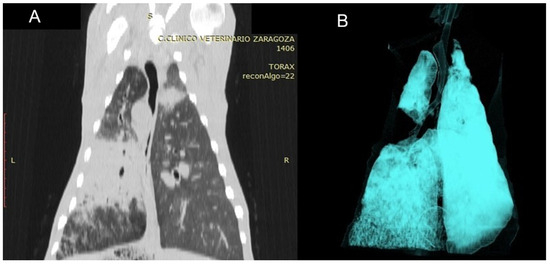

Use of Computed Tomography in the Clinical Diagnosis of Lower Respiratory Tract Diseases in Sheep

Lower airway diseases are a major health concern in sheep, often presenting with overlapping clinical signs that hinder accurate diagnosis. This study evaluated the diagnostic value of computed tomography (CT) in 58 adult sheep examined in northeastern Spain between 2017 and 2024. All animals underwent full clinical examination, CT under general anaesthesia, and post-mortem investigation. CT identified 82 pulmonary lesions, including interstitial pneumonia, respiratory complex, gangrenous pneumonia, caseous lymphadenitis, parasitic pneumonia, pulmonary adenocarcinoma, and pulmonary hydatidosis. Tissue density measurements provided additional information regarding disease stage and severity. The level of agreement between CT findings and definitive diagnoses consistently exceeded that of clinical evaluation, reaching almost perfect concordance for several conditions. Moreover, CT revealed concomitant respiratory pathologies within the same animal, many of which were not detected by conventional diagnostic methods. Although thorough individual clinical examination remains essential for the correct interpretation of imaging findings and the accurate diagnosis of respiratory disorders in the field, these results demonstrate that CT provides superior diagnostic accuracy compared with standard approaches and yields valuable insights for both clinical practice and research. Despite its practical limitations, CT could represent a major advance in improving health, welfare, and productivity in sheep farming. Full article